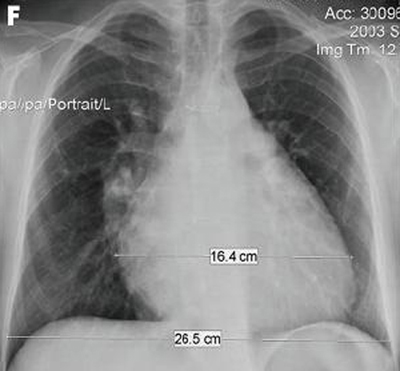

Chest x-ray in a patient with pulmonary regurgitation following repair of tetralogy of Fallot. The patient has a non-restrictive right ventricle and the heart is large

From: Chaturvedi RR, Redington AN. Heart. 2007 Jul;93(7):880-9; used with permission